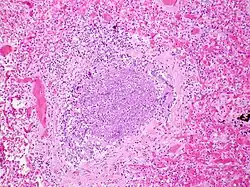

Bronchiolitis is most commonly caused by respiratory syncytial virus[7] (RSV, also known as human pneumovirus). Other agents that cause this illness include, but are not limited to, human metapneumovirus, influenza, parainfluenza, coronavirus, adenovirus, rhinovirus and mycoplasma.[12][13]

.jpg)